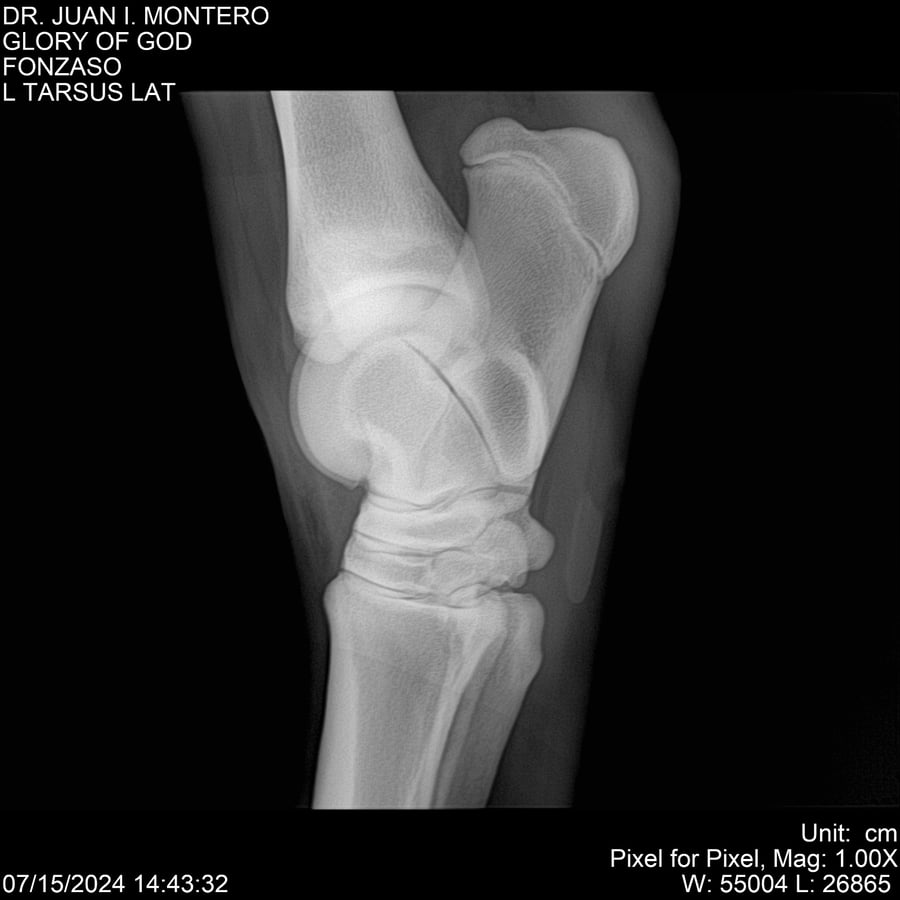

LOTE 10, GLORY OF GOD 🔥 🔥 🔥 Lote Anterior Volver al remate Lote Siguiente Ficha Contacto Montevideo - Ficha del Lote Identificador: #281389 Categoría: Yeguarizos Montevideo - 115 Visualizaciones ClicData Contacto Empresa: Abelenda N. R., Walter Hugo Nombre*: Teléfono* : E-mail* : Mensaje Enviar Registrese gratis Este contenido Exclusivo está disponible sólo para usuarios registrados Ingresar